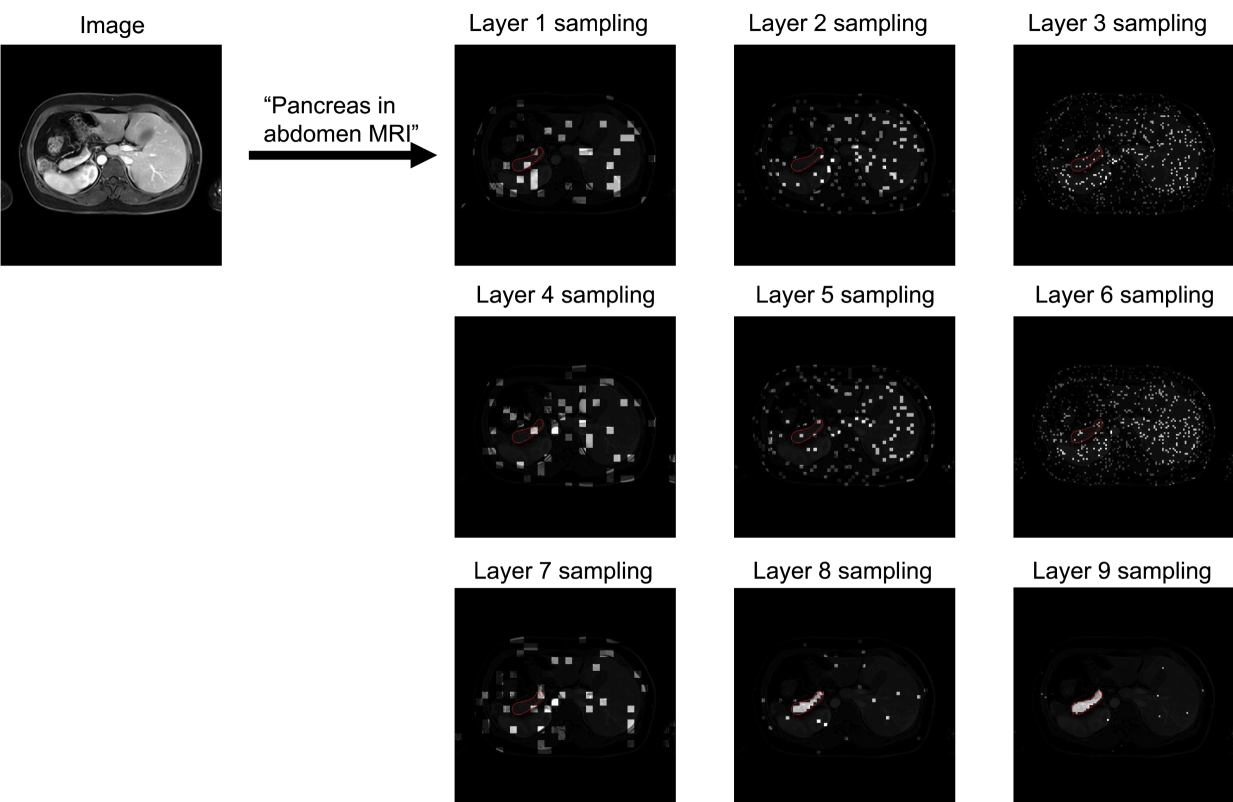

From Fig. 5, 6, 7 and 8 we can see that the sampling is wide spread during the early layers. The sampling began to concentrate towards the target region during the middle layers, while still exploring the other regions. At the final layers the sampling was highly concentrated on the target regions.

Figure 6: Boltzmann sampling example for pancreas in abdomen MRI. The sample patches are bright with target region circled in red.

We visualize the examples of Boltzmann attention sampling through the layers in BoltzFormer. In each layer, each query vector only attend to the sampled visual features visualized in the figures. We looped through the three scales of visual features for three times, resulting in nine layers in total. The shaded regions are completely invisible to the query in that layer. We show the Boltzmann sampling for the first query in the ensemble in these examples.